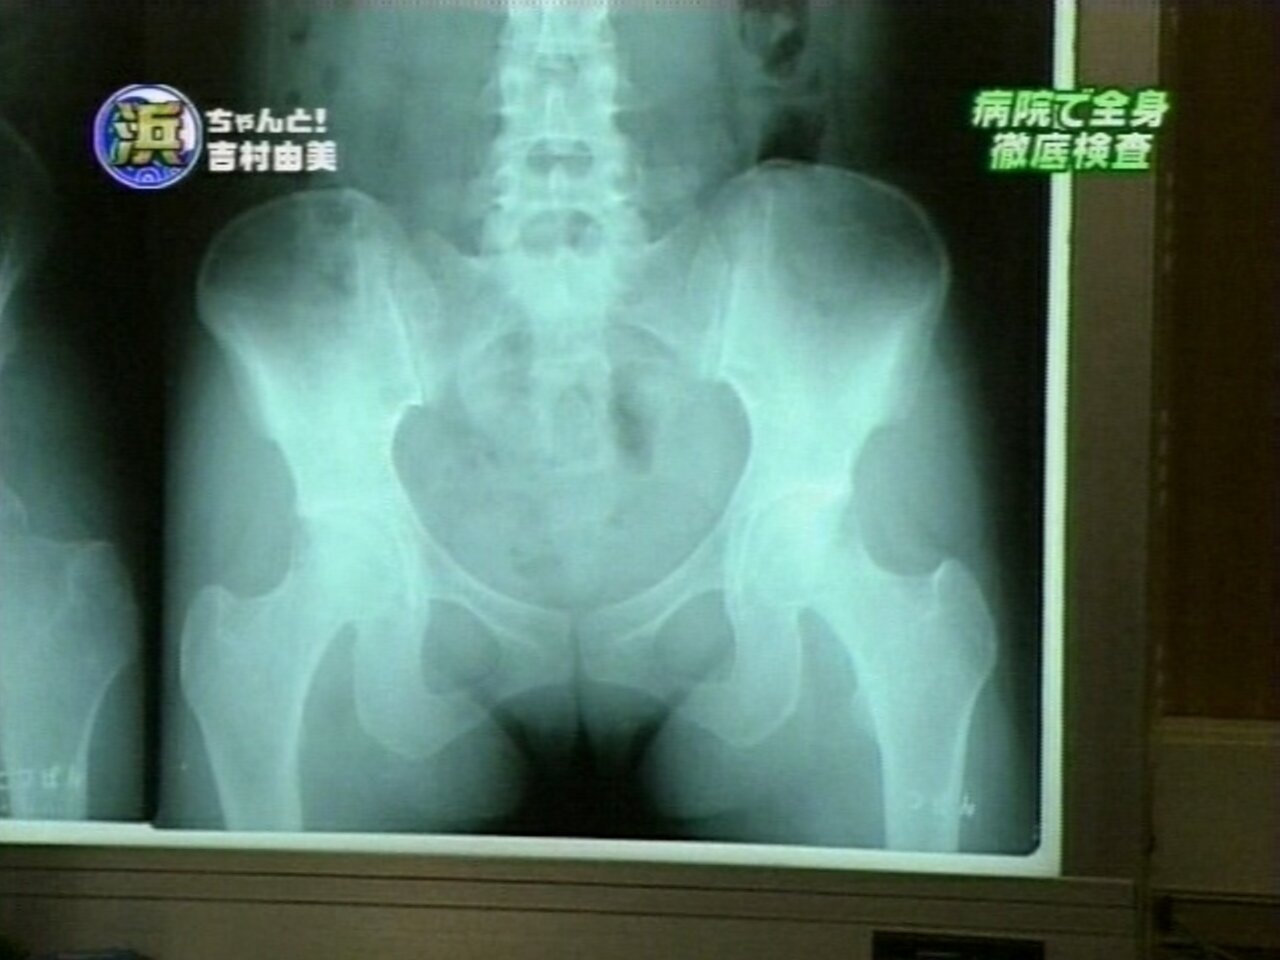

ペッサリー

子宮リングとか今時割と普通だろ

そもそも避妊リング入れてるの公表してるし

ミレーナな

生理痛緩和と3年くらい中●ししてもほぼ妊娠しないやつ

ミレーナってやつらしい

右に映ってるのが尾骶骨だろうけど、避妊具ってこの角度で入ってんの?